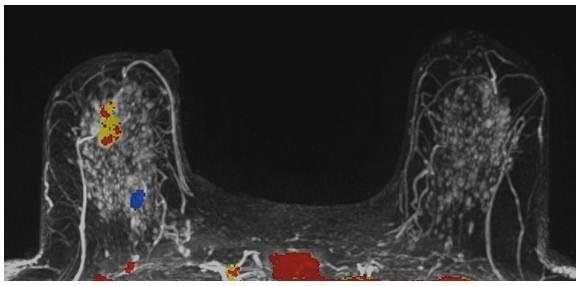

A 59-year-old female presented with a 3 cm palpable mass in the right breast. No identifiable abnormalities were identified on either the RMLO (on right) or RCC (on left) tomosynthesis images. (Image courtesy of Marc F. Inciardi, M.D., University of Kansas Medical Center)

Why perform different exams? By virtue of physics and tissue characteristics, imaging techniques may significantly differ in the characteristics of cancers detected. This can be seen in everyday practice with mammography, ultrasound and MRI of the breast. In fact, Hoff et al. demonstrated differences in the discernible features of cancer by comparing two similar modalities, FFDM and SFM.11 Using different supplemental tools to complement each other will result in improved sensitivity and specificity (see the images of a patient case on page 47 for an example).